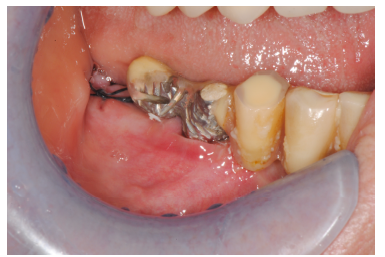

Despite regular check-ups over the years, peri-implantitis developed in the most distal implant in the right hemi-arch, despite the patient’s good oral hygiene. In January 2023, it was decided to intervene. The initial state of the affected implant pre-surgical treatment is visible in the intraoral image (Figure 2).

Figure 2